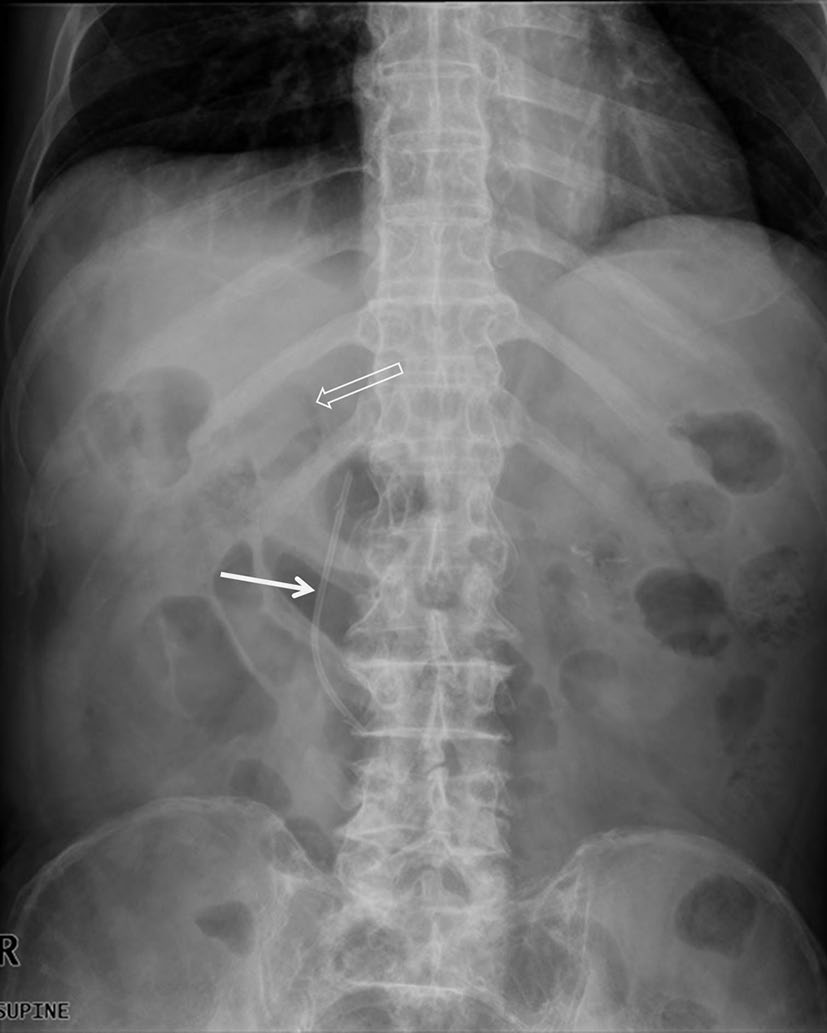

持续性不卧床腹膜透析导管

持续性非卧床腹膜透析(CAPD)主要用于治疗终末期肾衰竭患者(图8)[8]。在导管置入过程中,腹膜透析导管的远端尖端应置于盆腔内的低位位置,以确保透析液交换时充分流出。导管尖端从盆腔迁移出来会导致透析液流出受阻和液体引流不充分(图9)。据报道,该事件在导管置入后1年内的发生率为57%[8]。